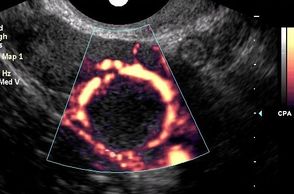

The corpus luteum shows typical features on ultrasound. The corpus luteum is a thick walled cyst with characteristic "ring of fire" peripheral vascularity. It usually has a crenulated inner margin and internal echoes. Identification of a corpus luteum is evidence that ovulation has occurred. On the other hand, failure to demonstrate a corpus luteum suggests that ovulation has not occurred.